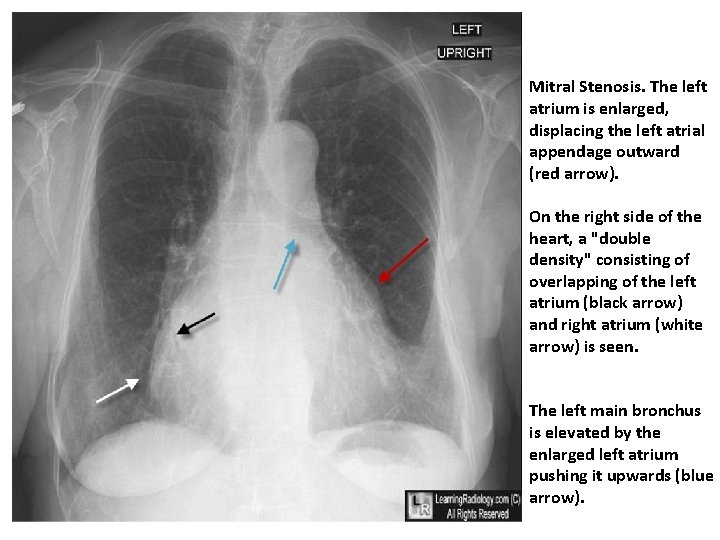

Mitral Stenosis. The left atrium is enlarged, displacing the left atrial appendage outward (red arrow). On the right side of the heart, a "double density" consisting of overlapping of the left atrium (black arrow) and right atrium (white arrow) is seen. The left main bronchus is elevated by the enlarged left atrium pushing it upwards (blue arrow).

Investigations –X-ray • Small heart with an enlarged L/ atrium • Pulmonary venous hypertension • Calcified mitral valve– on penetrated or lateral view • Signs of pulmonary oedema or pulmonary hypertension JMJ 19

Diagnosis ECG Tall R-waves (V 1 -V 3) RV hypertrophy P mitrale or atrial fibrillation Imaging X-ray (chest) Enlarged LA & appendage Signs of pulmonary venous congestion Echocardiography Thickened immobile cusps Reduced valve area Enlarged LA ↓ LV diastolic filling Doppler (DEFINITIVE) Pressure gradient across mitral valve Pulmonary artery pressure Left ventricular function Cardiac catheterisation

Complications Hemoptysis, pulmonary embolism, pulmonary infection, systemic embolization; endocarditis is uncommon in pure MS. Laboratory ECG Typically shows atrial fibrillation (AF) or left atrial (LA) enlargement when sinus rhythm is present. Right-axis deviation and RV hypertrophy in the presence of pulmonary hypertension. CXR Shows LA and RV enlargement and Kerley B lines. Echocardiogram Most useful noninvasive test; shows reduced separation, calcification and thickening of valve leaflets and subvalvular apparatus, and LA enlargement. Doppler flow recordings provide estimation of transvalvular gradient, mitral valve area, and degree of pulmonary